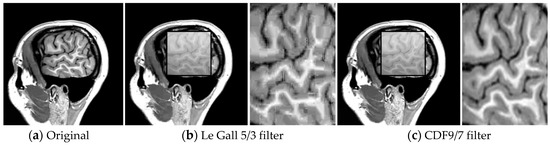

In this experiment, MRI video is encoded using the Bandelet-SPIHT algorithm for various bit rates. In order to find the most suitable wavelet filter for different test images based upon objective quality measures for video compression, biorthogonal family was considered. Thus, biorthogonal wavelets CDF (Cohen–Daubechies–Feauveau) 9/7 (nine coefficients in decomposition low-pass and seven in decomposition highpass filters) and Le Gall 5/3 (five coefficients in decomposition low-pass and three in decomposition high-pass filters) are selected.

The choice of these filters is justified by their simplicity, symmetry and their compact support (localization in space).

By a subjective quality assessment of images shown in Figure 8, we opt for CDF 9/7, which reduces the level of artifacts. Indeed, the obtained results show that the recovered frame using the bandelet algorithm + SPIHT is close to the original frame.

Figure 8.

Recovered frames using: (b) Bandelet (Le Gall 5/3)-SPIHT and (c) Bandelet (CDF9/7)-SPIHT at 0.2 Mbps.

It is worth noting the presence of blurred areas in the image when Le Gall 5/3 filters are used.